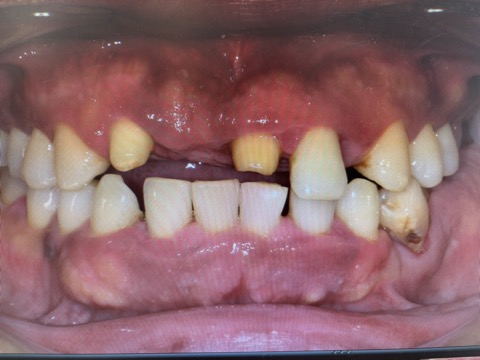

最近拝見した患者様の中でかなり重症だった方です。

写真は正面観で、前歯ももちろん瀕死の状態でしたが、奥歯がもっと重症で、食いしばりが酷いために歯周病が悪化して4本も抜かなければいけない状態でした。

そして抜くだけではダメで、下がってしまった噛み合わせを挙上していく必要がありました。

奥歯と前歯の仮歯をチェアサイドで2時間で作り、まずは日常生活に不具合がないところまで整えて、